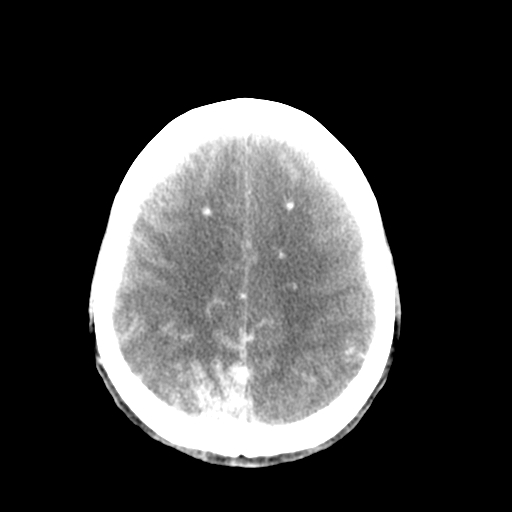

标题: CT17002:M48Y,血管畸形,血管瘤,请鉴赏! [打印本页]

男48y,头痛多年,加重一天!

典型的血管畸形---avm  -----右侧枕顶叶及侧脑室三角区等高混杂密度影夹杂少许低密影显示,无明显水肿,增强可见明显的供血动脉与引流静脉显示